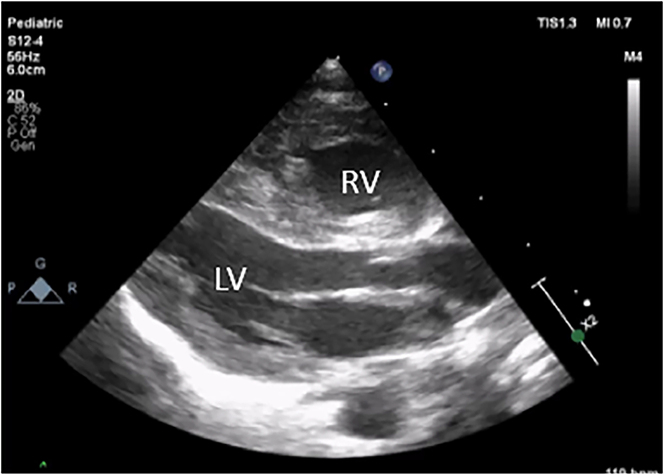

Case presentation: A term infant was diagnosed with severe PPHN with echocardiographic features noted at 6 h after birth which included supra-systemic pulmonary pressures, severe isolated right ventricle (RV) hypertrophy, poor RV dysfunction and no ductal flow in the context of a structurally normal heart. There was maternal use of low-dose aspirin in pregnancy due to preeclampsia. There is a known association between use of prostaglandin synthase inhibitors such as aspirin with ductal closure leading to increased RV pressure. Treatment was commenced with positive pressure ventilation, inhaled nitric oxide (iNO) and milrinone. There was a limited response to iNO necessitating increasing the concentration of milrinone with a marked improvement in oxygenation. Following commencement of sildenafil, inhaled nitric oxide was gradually weaned and stopped in the third week and the infant extubated. The infant was discharged home on oral sildenafil at four weeks of age with no respiratory or feeding support. Echocardiographic features of raised right sided pressures persisted, but with reduced RV hypertrophy and septal flattening and improved RV function. Oral sildenafil was subsequently weaned and stopped at four months of age.